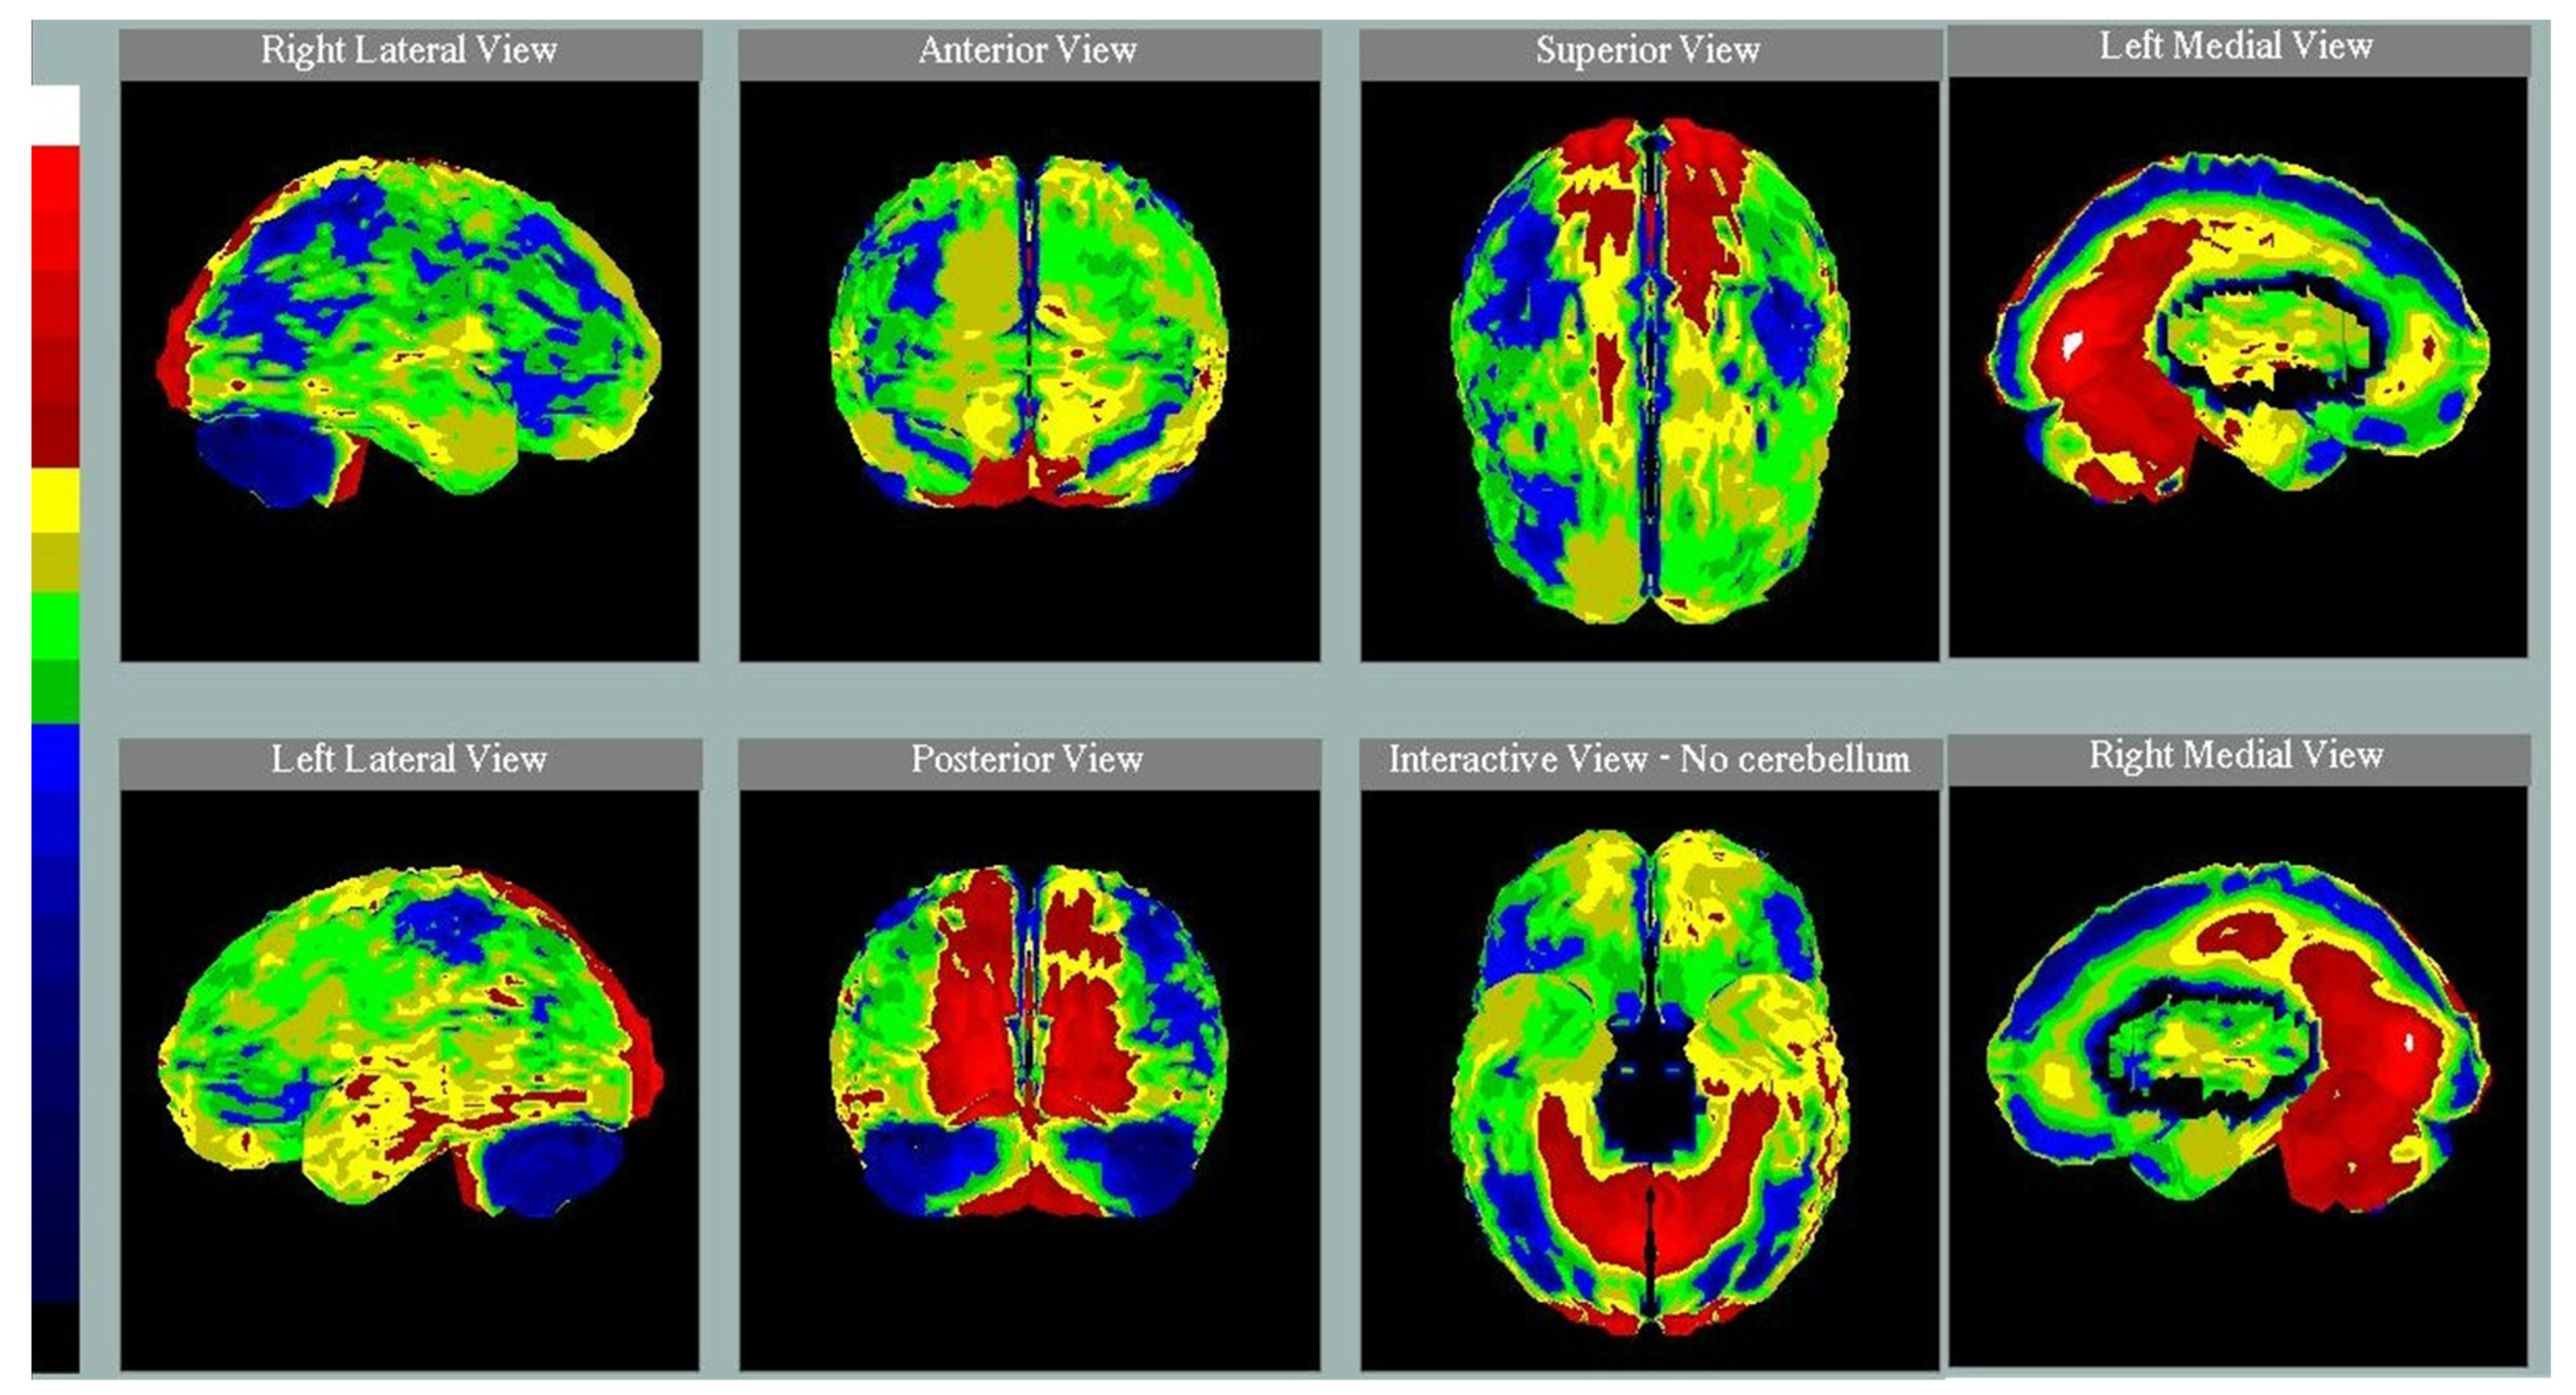

2.2. SPECT Studies